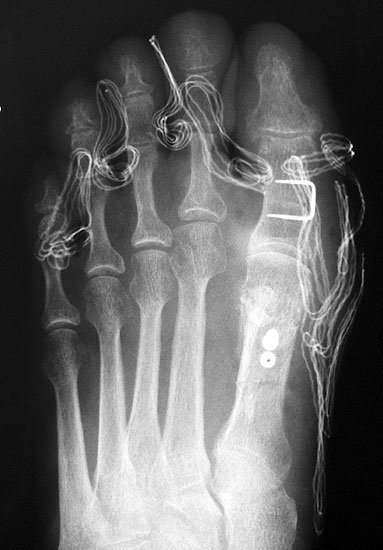

Die dorsoplantaren Röntgenaufnahmen zeigen eine Open-wedge Technik mit der normalerweise ein erhöhter intermetatarsaler Winkel gut zu korrigieren ist (Abbildung 3). Die Wirksamkeit einer Basisosteotomie ist umso größer, je proximaler diese durchgeführt wird. Je weiter distal die Osteotomie, umso geringer die Korrektur. Auf den postoperativen Bildern ist der distal unverändert große Abstand zwischen Metatarsale I und Metatarsale II erkennbar, bei gleichzeitiger Subluxation des Großzehengrundgelenks und dezentrierten Sesambeinen. Darüber hinaus finden sich initiale degenerative Veränderungen im Großzehengrundgelenk. Klinisch bestand eine hohe Weichteilspannung, bei verkürzter Extensor- und Flexor hallucis longus Sehne.  Daher wurde ein verkürzendes Verfahren zur Revision gewählt (Abbildung 4). Die Lapidusarthrodese stellt ein sehr zuverlässiges Verfahren zur Behandlung von Hallux valgus Rezidiven dar 9. Die Fusion des Tarsometatarsale-I-Gelenks kombiniert Stabilität mit einem hohen Korrekturpotenzial. Aufgrund der verfahrensimmanenten Verkürzung des ersten Strahls und der in diesem Fall bereits präoperativ vorhandenen Transfermetatarsalgie wurde die Entscheidung für eine verkürzte Weil-Osteotomie am zweiten bis fünften Strahl gefällt. Die Kombination beider Verfahren führte zu einem homogenen Metatarsale-Index und zu einer gleichmäßigen plantaren Druckverteilung 10. Die Hallux valgus interphalangeus Fehlstellung wurde mit einer Akin-Osteotomie korrigiert.